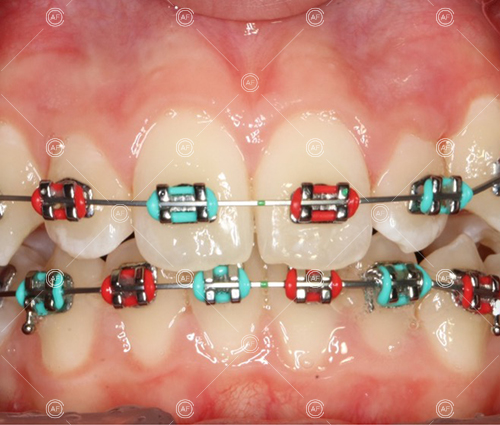

Treatment progressed by starting with thin, flexible nickel titanium archwires of a round diameter, transitioning to a rectangular nickel titanium archwire before eventually working up to a working archwire (1925 stainless steel).

Residual space from the extractions were closed using upper and lower nickel titanium closing coils. Class 2 elastics were used to facilitate space closure in order to gain class 1 buccal segments.